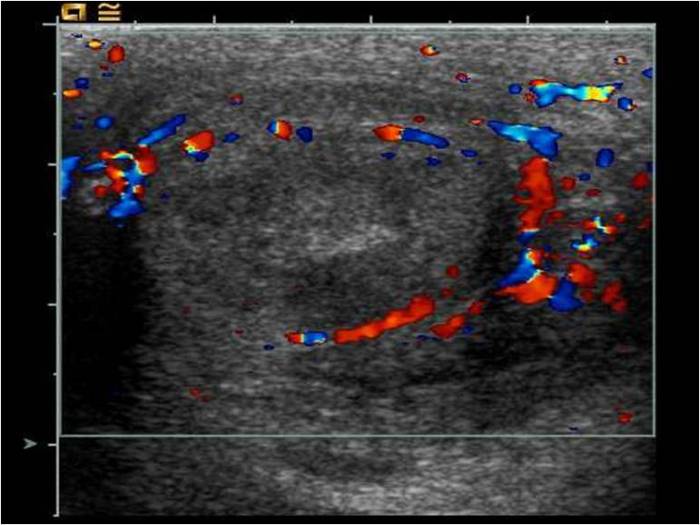

Другой, не менее распространенной причиной манифестации воспаления тестикула, является нарушение трофики тканей яичка, которые возникают по причине перекрута семенного канатика, в котором проходят сосуды, ответственные за кровоснабжение яичка.